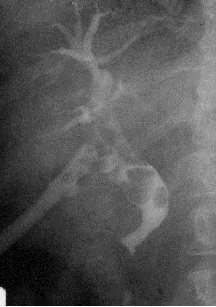

Рис. 10. Рентгенограмма пищевода в правой косой проекции. Тень пищевода расширена вследствие рака его нижнегрудного отдел а.